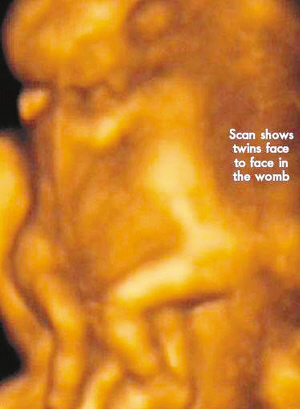

今年初,懷孕7周多的麗莎檢查發現,懷上的竟是一對腹部緊緊相連的連體男嬰。這對連體嬰共享一只肝臟,雖然他們擁有各自的心臟,但兩顆心臟卻粘連在了一起。醫生建議麗莎立即接受流產手術,他認為麗莎腹中的連體嬰甚至無法活到她懷孕10周的時候。

麗莎每周都要到醫院接受醫學掃描,而她腹中的連體嬰也讓醫生感到驚訝不已,因為他們已經打破了醫生的死亡預言,一直在母親子宮中堅強活到了現在。麗莎將于兩周內接受剖腹產手術。